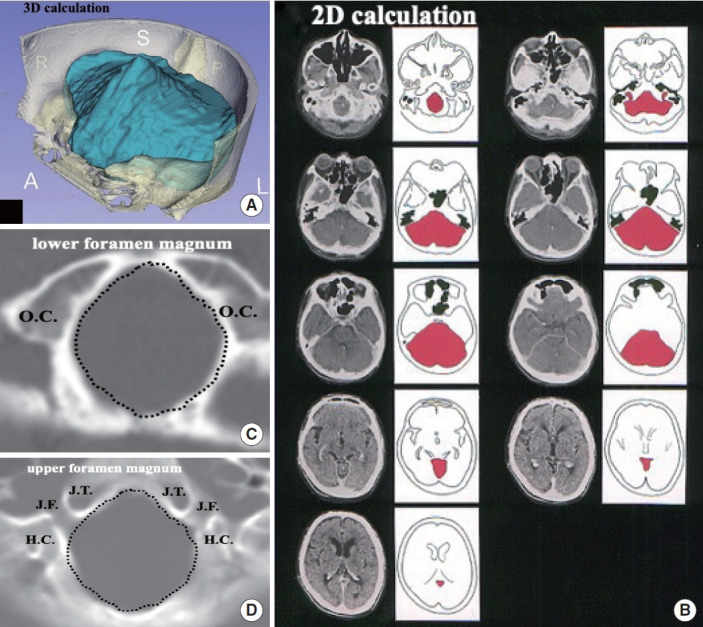

H. Chiari描述了4种后窝异常发育类型,随后将其分类为Chiari畸形I型、II型、III型和IV型。神经外科中关于分类和手术处理的许多问题没有发展的概念。本文旨在阐明后脑(脑干和小脑)下降的机制和发病机制,对其进行分类,并讨论适当的手术治疗。我们提出了4种独立致病机制的分类:(1)由于枕骨发育不全导致后颅窝(PCF)收缩;(2)后脑肿大;(3)牵系病变引起的牵引。我们从胚胎学和神经放射学的角度研究后脑下降的发病机制,特别关注鲜为人知的机制。此外,第四种机制被提出:(4)颅颈交界处不稳定。我们建议基于潜在的发病机制,在形态测量学(枕骨大小)和体积(PCF体积)分析的指导下,对I型Chiari畸形进行新的分类。此外,它通过借鉴发育生物学、遗传研究和实验研究的见解,深入研究了它们的发病机制。针对潜在机制,我们提出了手术干预决策算法。对于由于枕骨发育不全导致的PCF拥挤,后颅窝减压是合适的手术干预。对于颅颈不稳定,建议采用枕颈固定。我们还回顾了与每种治疗方法相关的手术结果的最新文献。最后,我们重点介绍了目前与后脑下降发病机制有关的遗传学研究。

H. Chiari described 4 types of abnormal development of the posterior fossa, which were subsequently classified as Chiari malformation types I, II, III, and IV. Many issues in neurosurgery concerning classification and surgical management are without evolving concepts. This review aims to clarify the mechanisms and pathogenesis underlying hindbrain (the brain stem and cerebellum) descent, classify them accordingly, and discuss appropriate surgical management. We propose a classification of 4 independent pathogenic mechanisms: (1) constriction in the posterior cranial fossa (PCF) due to underdevelopment of the occipital bone; (2) enlargement of hindbrain; and (3) traction caused by tethering lesions. We examine the pathogenesis of hindbrain descent from embryological perspectives and neuroradiological findings, with a particular focus on lesser-known mechanisms. Additionally, another fourth mechanism is proposed: (4) instability at the craniocervical junction. We suggest a novel classification for Chiari malformation type I based on the underlying pathogenesis, guided by morphometric (occipital bone size) and volumetric (PCF volume) analyses. Furthermore, it delves deeper into their pathogenesis by drawing on insights from developmental biology, genetic studies, and experimental research. Surgical management is tailored to the underlying mechanism, and we proposed the algorithm for decision of surgical intervention. For crowding of the PCF due to underdevelopment of the occipital bone, posterior fossa decompression is the appropriate surgical intervention. For craniocervical instability, occipitocervical fixation is recommended. We also review the recent literature on surgical outcomes associated with each treatment approach. Finally, we highlight current genetic research related to the pathogenesis of hindbrain descent.